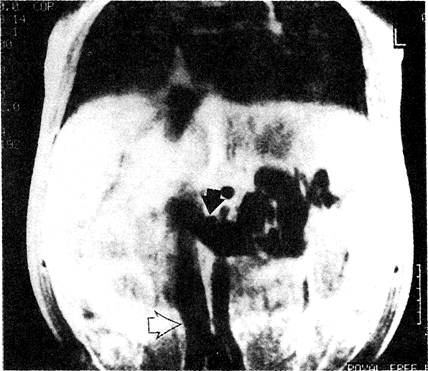

Магнитно-резонансная томо­грамма. Выявлен спонтанный спленоренальный шунт, впадающий в нижнюю полую вену. Видны почечная (указана чёр­ной стрелкой) и нижняя полая (указана светлой стрелкой) вены.